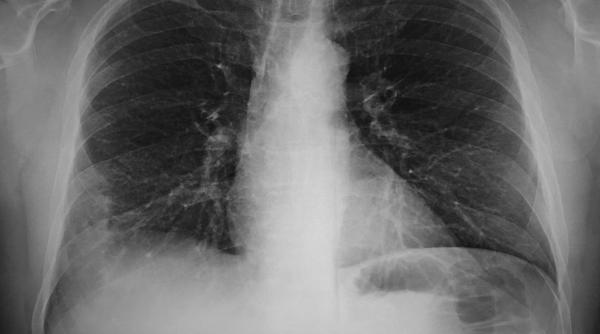

La fiecare 50 de minute, un român este diagnosticat cu cea mai mortală boală infecțioasă din lume: TBC

„Catastrofa globală” veche de 140 de ani. Tuberculoza: Un nou test rapid ar putea detecta milioane de transmițători silențioși